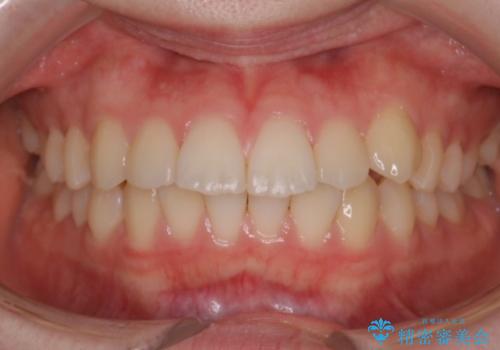

前歯の乱れをスッキリ解消!抜歯矯正で整えた美しい歯並び

担当医 河口智英